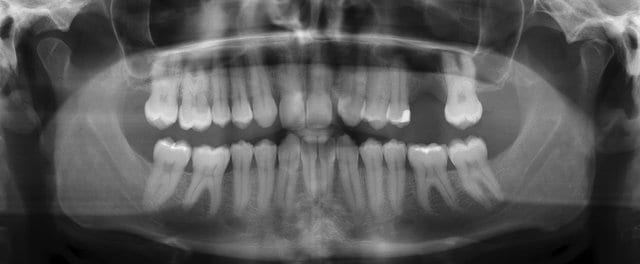

If you are missing the second largest molar, and both the upper and lower ones are missing, and if it does not affect your bite and chewing because there is no corresponding opposing tooth, in this case, you do not need to get dentures or dental implants. However, if you are only missing one second molar and the corresponding second molar is still there, it is a different situation and reconstruction is necessary.

It is recommended that reconstruction is necessary, otherwise the adjacent teeth will tilt to the left and right, and the antagonistic teeth will extend toward the missing teeth.The back teeth cannot be seen, so why do they need reconstruction?To answer the above situation, why is reconstruction necessary if only the second molar is missing? Since the back teeth cannot be seen, why do we need to fill them? That is because the corresponding opposing teeth will extend towards the missing teeth, thus creating a height difference. If the teeth are not straight, there will be a blind spot for cleaning, which will almost always cause new caries on the adjacent teeth. . In addition, when the second molar extends toward the missing tooth, it is easy to cause the tooth root to be exposed, resulting in sensitivity and discomfort. Therefore, even if the back teeth are not visible, they still need to be treated in this situation to avoid subsequent problems.